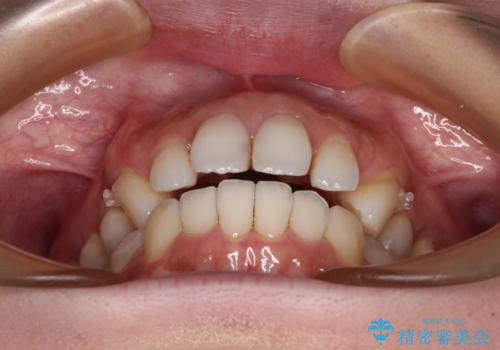

- デコボコと飛び出している前歯を気にして来院された患者様です。

歯列としてはインビザラインでもワイヤー矯正でも対応できるものでしたが、奥歯の咬み合わせを見た時に上顎がやや前方にあり、インビザライン単独では時間のかかってしまう可能性があるため、補助装置を治療当初に使用することで、インビザラインによる治療をスムーズに行えるように計画しました。

インビザラインは得意・不得意の差がはっきりとしているため、補助装置やワイヤー装置などをうまく活用することで、治療期間を短縮するとともに、より理想的な仕上がりを達成することができます。